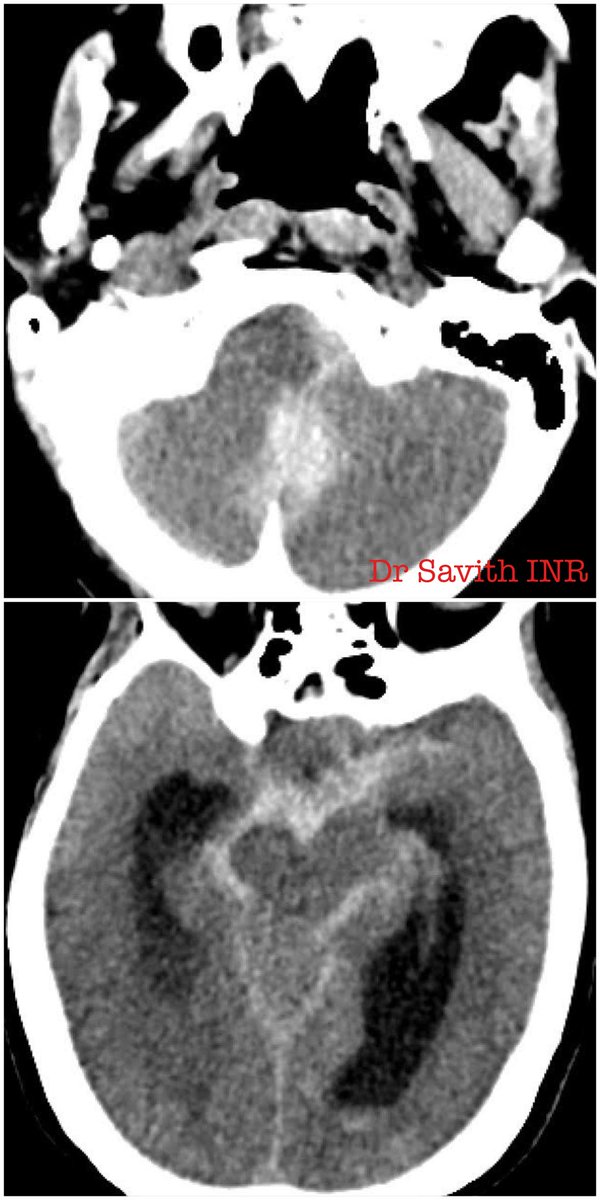

60 year old female with SAH and hydrocephalus from ruptured left PICA dissecting aneurysm. Partent artery occlusion done followed by EVD. Follow up CT showed left PICA territory infarct. Neurological stable. #aneurysm #neurointervention #coiling